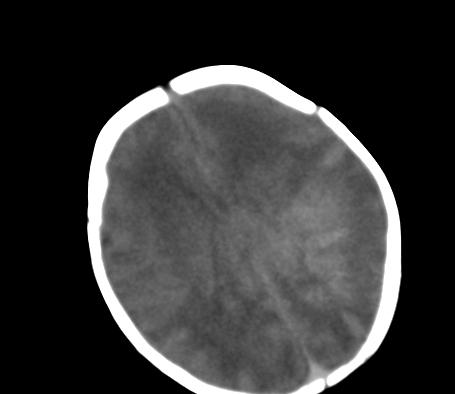

标题: PED0831:患儿,5天,是HIE吗?

患儿,出生时正常,第5天突然呕吐两次,无发热及抽搐。

片示:双侧大脑半球脑实质密度降低,皮髓分界尚清,左侧顶部脑沟内见铸形高密度影,脑中线结构居中。

2、hie并少量蛛网膜下腔出血。